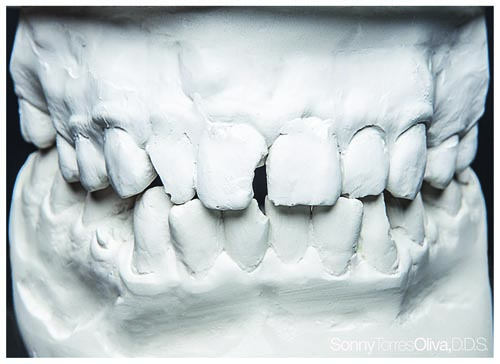

Fig. 11: Preoperative models were mounted, studied and used to determine ratios that should be incorporated into the restoration designs.